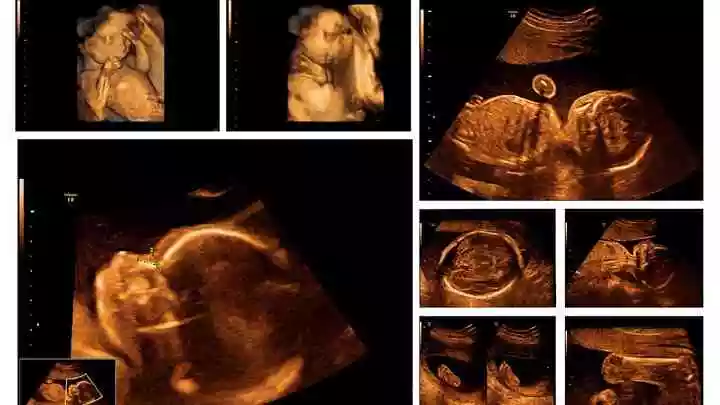

提起四维彩超如何看是女儿还是儿子,大家都知道,有人问怎么算出怀的男孩女孩,从哪些方面看的啊?,另外,还有人想问看四维彩超男孩女孩,你知道这是怎么回事?其实怎样通过四维彩超判断男孩还是女孩,下面就一起来看看怎么算出怀的男孩女孩,从哪些方面看的啊?,希望能够帮助到大家!

四维彩超如何看是女儿还是儿子

1、怎么算出怀的男孩女孩,从哪些方面看的啊?

怎样通过四维彩超判断男孩还是女孩

2、看四维彩超男孩女孩

3、怎样通过四维彩超判断男孩还是女孩

现在有很多的准爸妈是为了鉴别胎儿性别从而进行的四维彩超检查,这样的话,毫无意义。其实,无论是男孩或是女孩都是夫妻爱情的结晶,准爸妈们更应该关心胎儿是否健康、发育是否正常等因素,而不是在乎性别与否。

4、四维彩超图片是不是额头宽的是女儿窄的是儿子